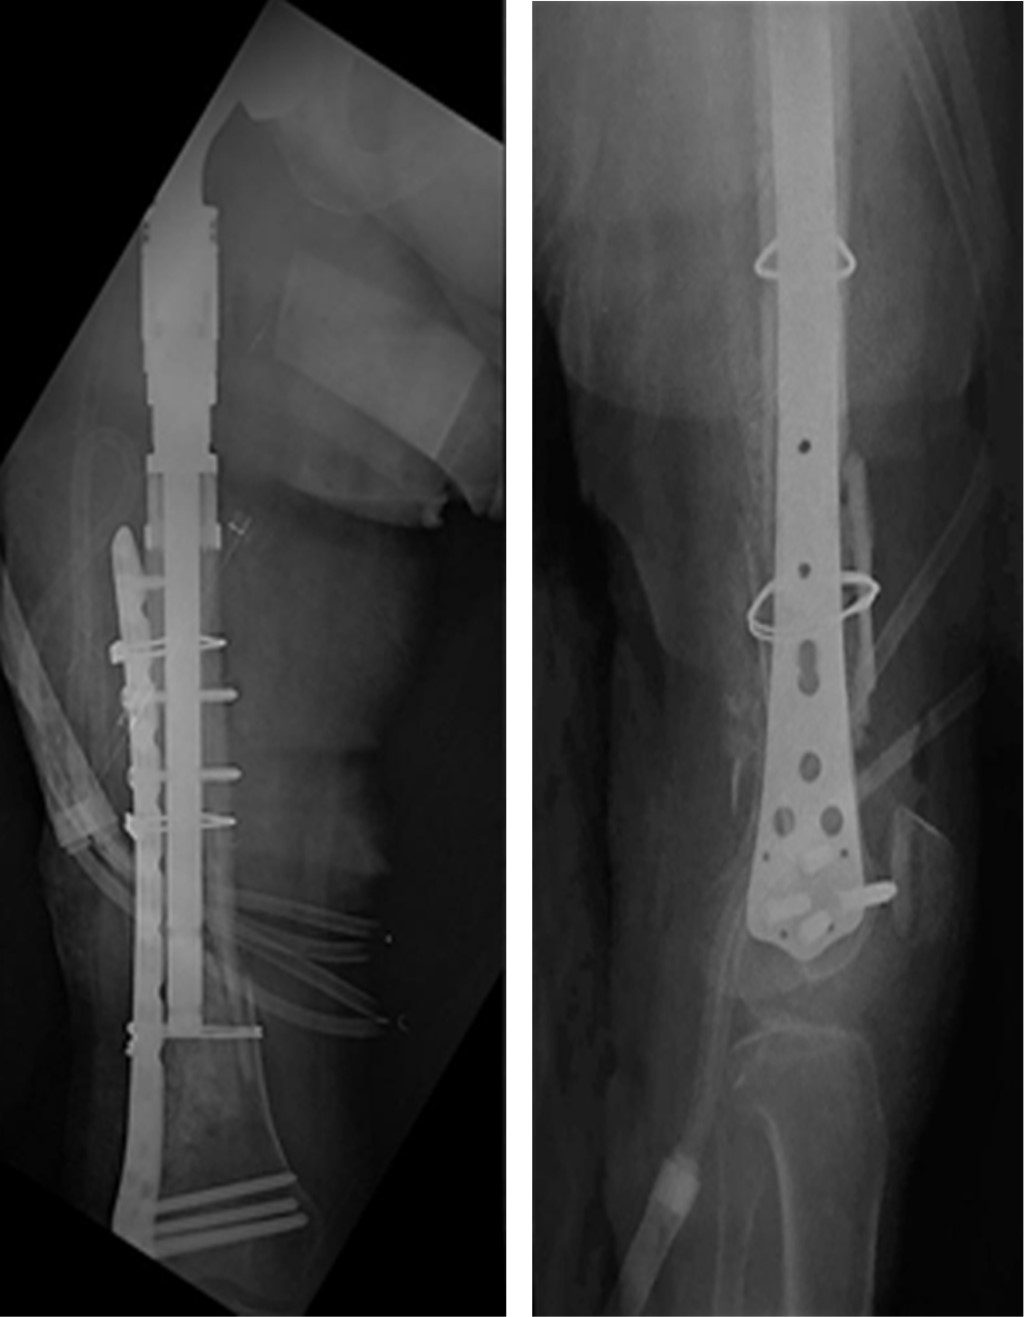

Bone metastases from a primary cancer of any part of the body are the most common form of malignant bone tumor constituting approximately 70% of them. The proximal femur being the most common extra-vertebral location for its location; 10% of patients have some pathological fracture, which is a serious complication. Currently the objectives of the treatment of a pathological fracture are: resection with adequate oncological margins, that the patient survives the surgical intervention, maintain the functionality, that the placed implant has a longer life time than the patient. The use of non-conventional hip prostheses is an excellent treatment option fulfilling the 4 established objectives, therefore this case is presented in which a right bipolar hip hemiarthroplasty is performed with a non-conventional prosthesis where it was treated with a described complication and the surgery of resolution.

Figure 2

Figure 3